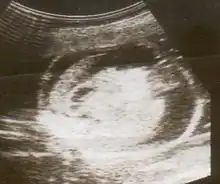

| An ultrasound showing a fetus with hydrops fetalis | |

Hydrops fetalis or hydrops foetalis is a condition in the fetus characterized by an accumulation of fluid, or edema, in at least two fetal compartments.[1][2] By comparison, hydrops allantois or hydrops amnion is an accumulation of excessive fluid in the allantoic or amniotic space, respectively.[3]

Hydrops fetalis can be diagnosed and monitored by ultrasound scans.[1] An official diagnosis is made by identifying excess serous fluid in at least one space (ascites, pleural effusion, of pericardial effusion) accompanied by skin edema (greater than 5 mm thick). A diagnosis can also be made by identifying excess serous fluid in two potential spaces without accompanying edema. Prenatal ultrasound scanning enables early recognition of hydrops fetalis and has been enhanced with the introduction of MCA Doppler.[7]